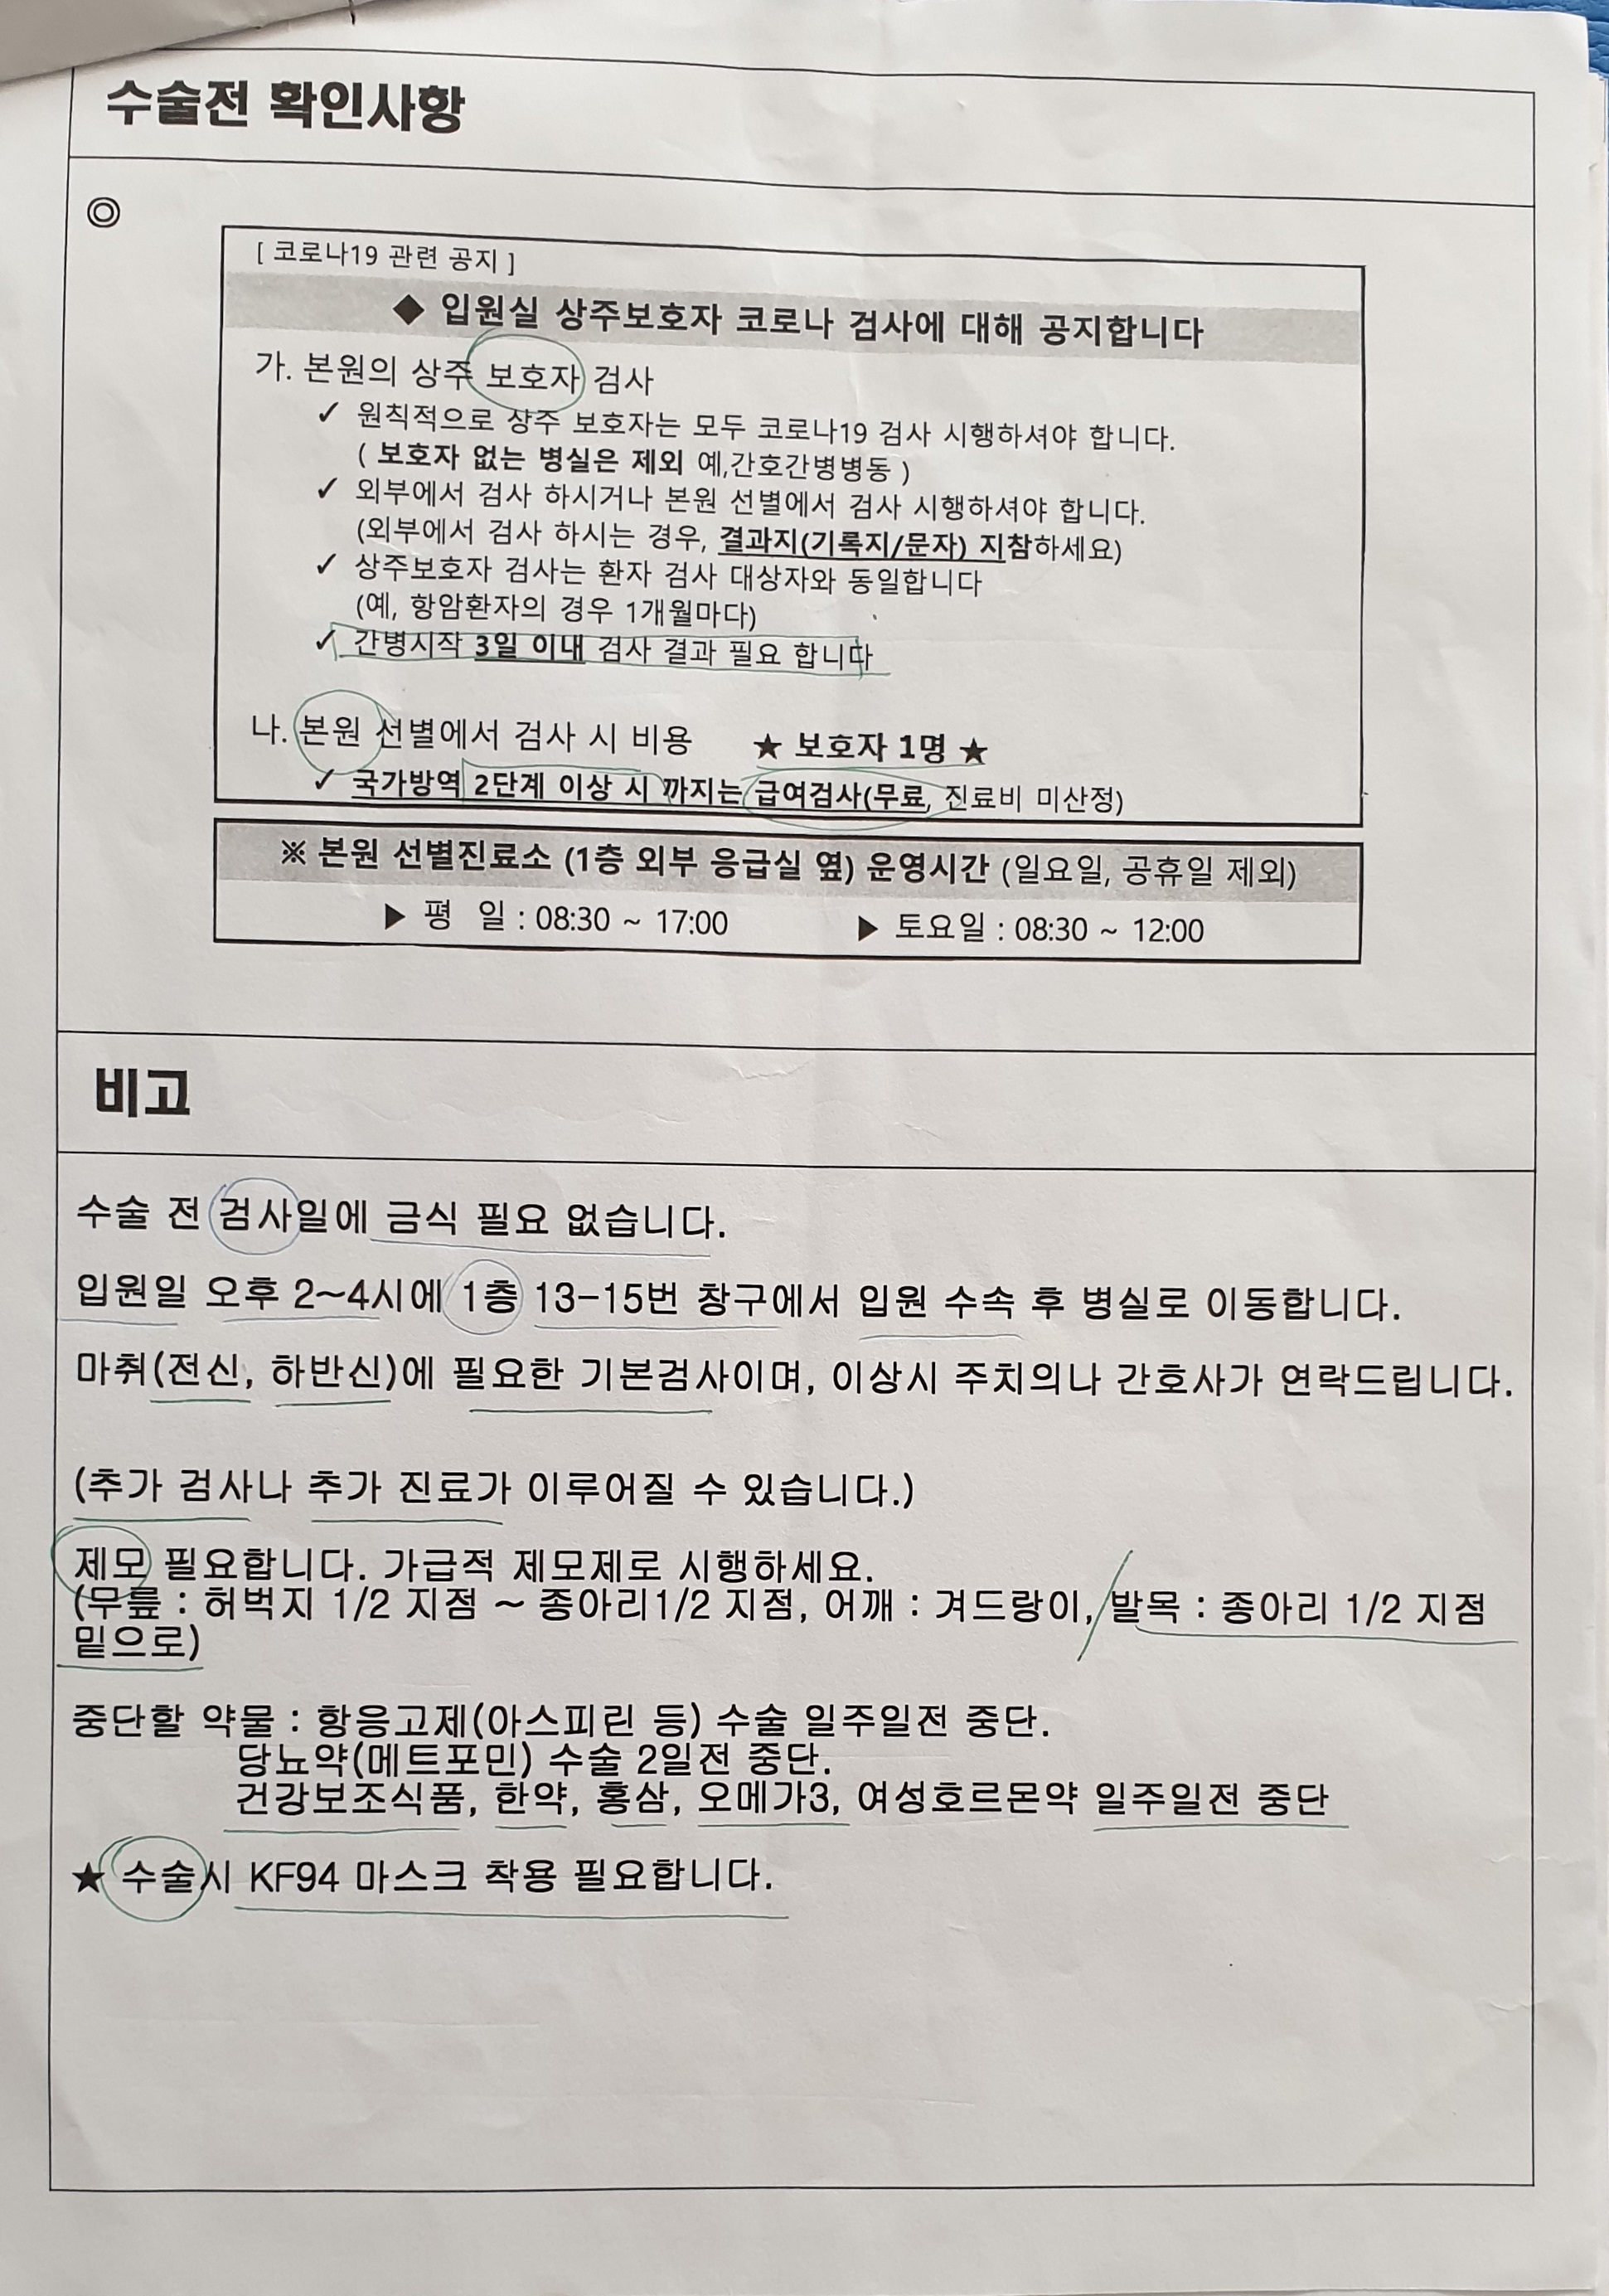

또 수술전 검사를 12일 하자고...

그러면서 수술전 진료일은 없다며 수납후 검사를 받으면 된다 한다.

11월 12일.............

16시까지 와서 수납후 검사를 받으라는 통보에 아마도 도착이 15시 30분쯤 되었지 싶다.

수납하는데 1,262,650원이다.

영상의학과에서 가슴사진과 골밀도 사진을

그리고 수납옆 창구에서 입원 예약을

또 채혈실에서 채혈및 소변 검사를

그리고 심전도 검사

영상의학과에서 17시 30분 예약 되어 있는 MRI검사를....

마치고 나오는데 18시 30분쯤 되었지 싶다.